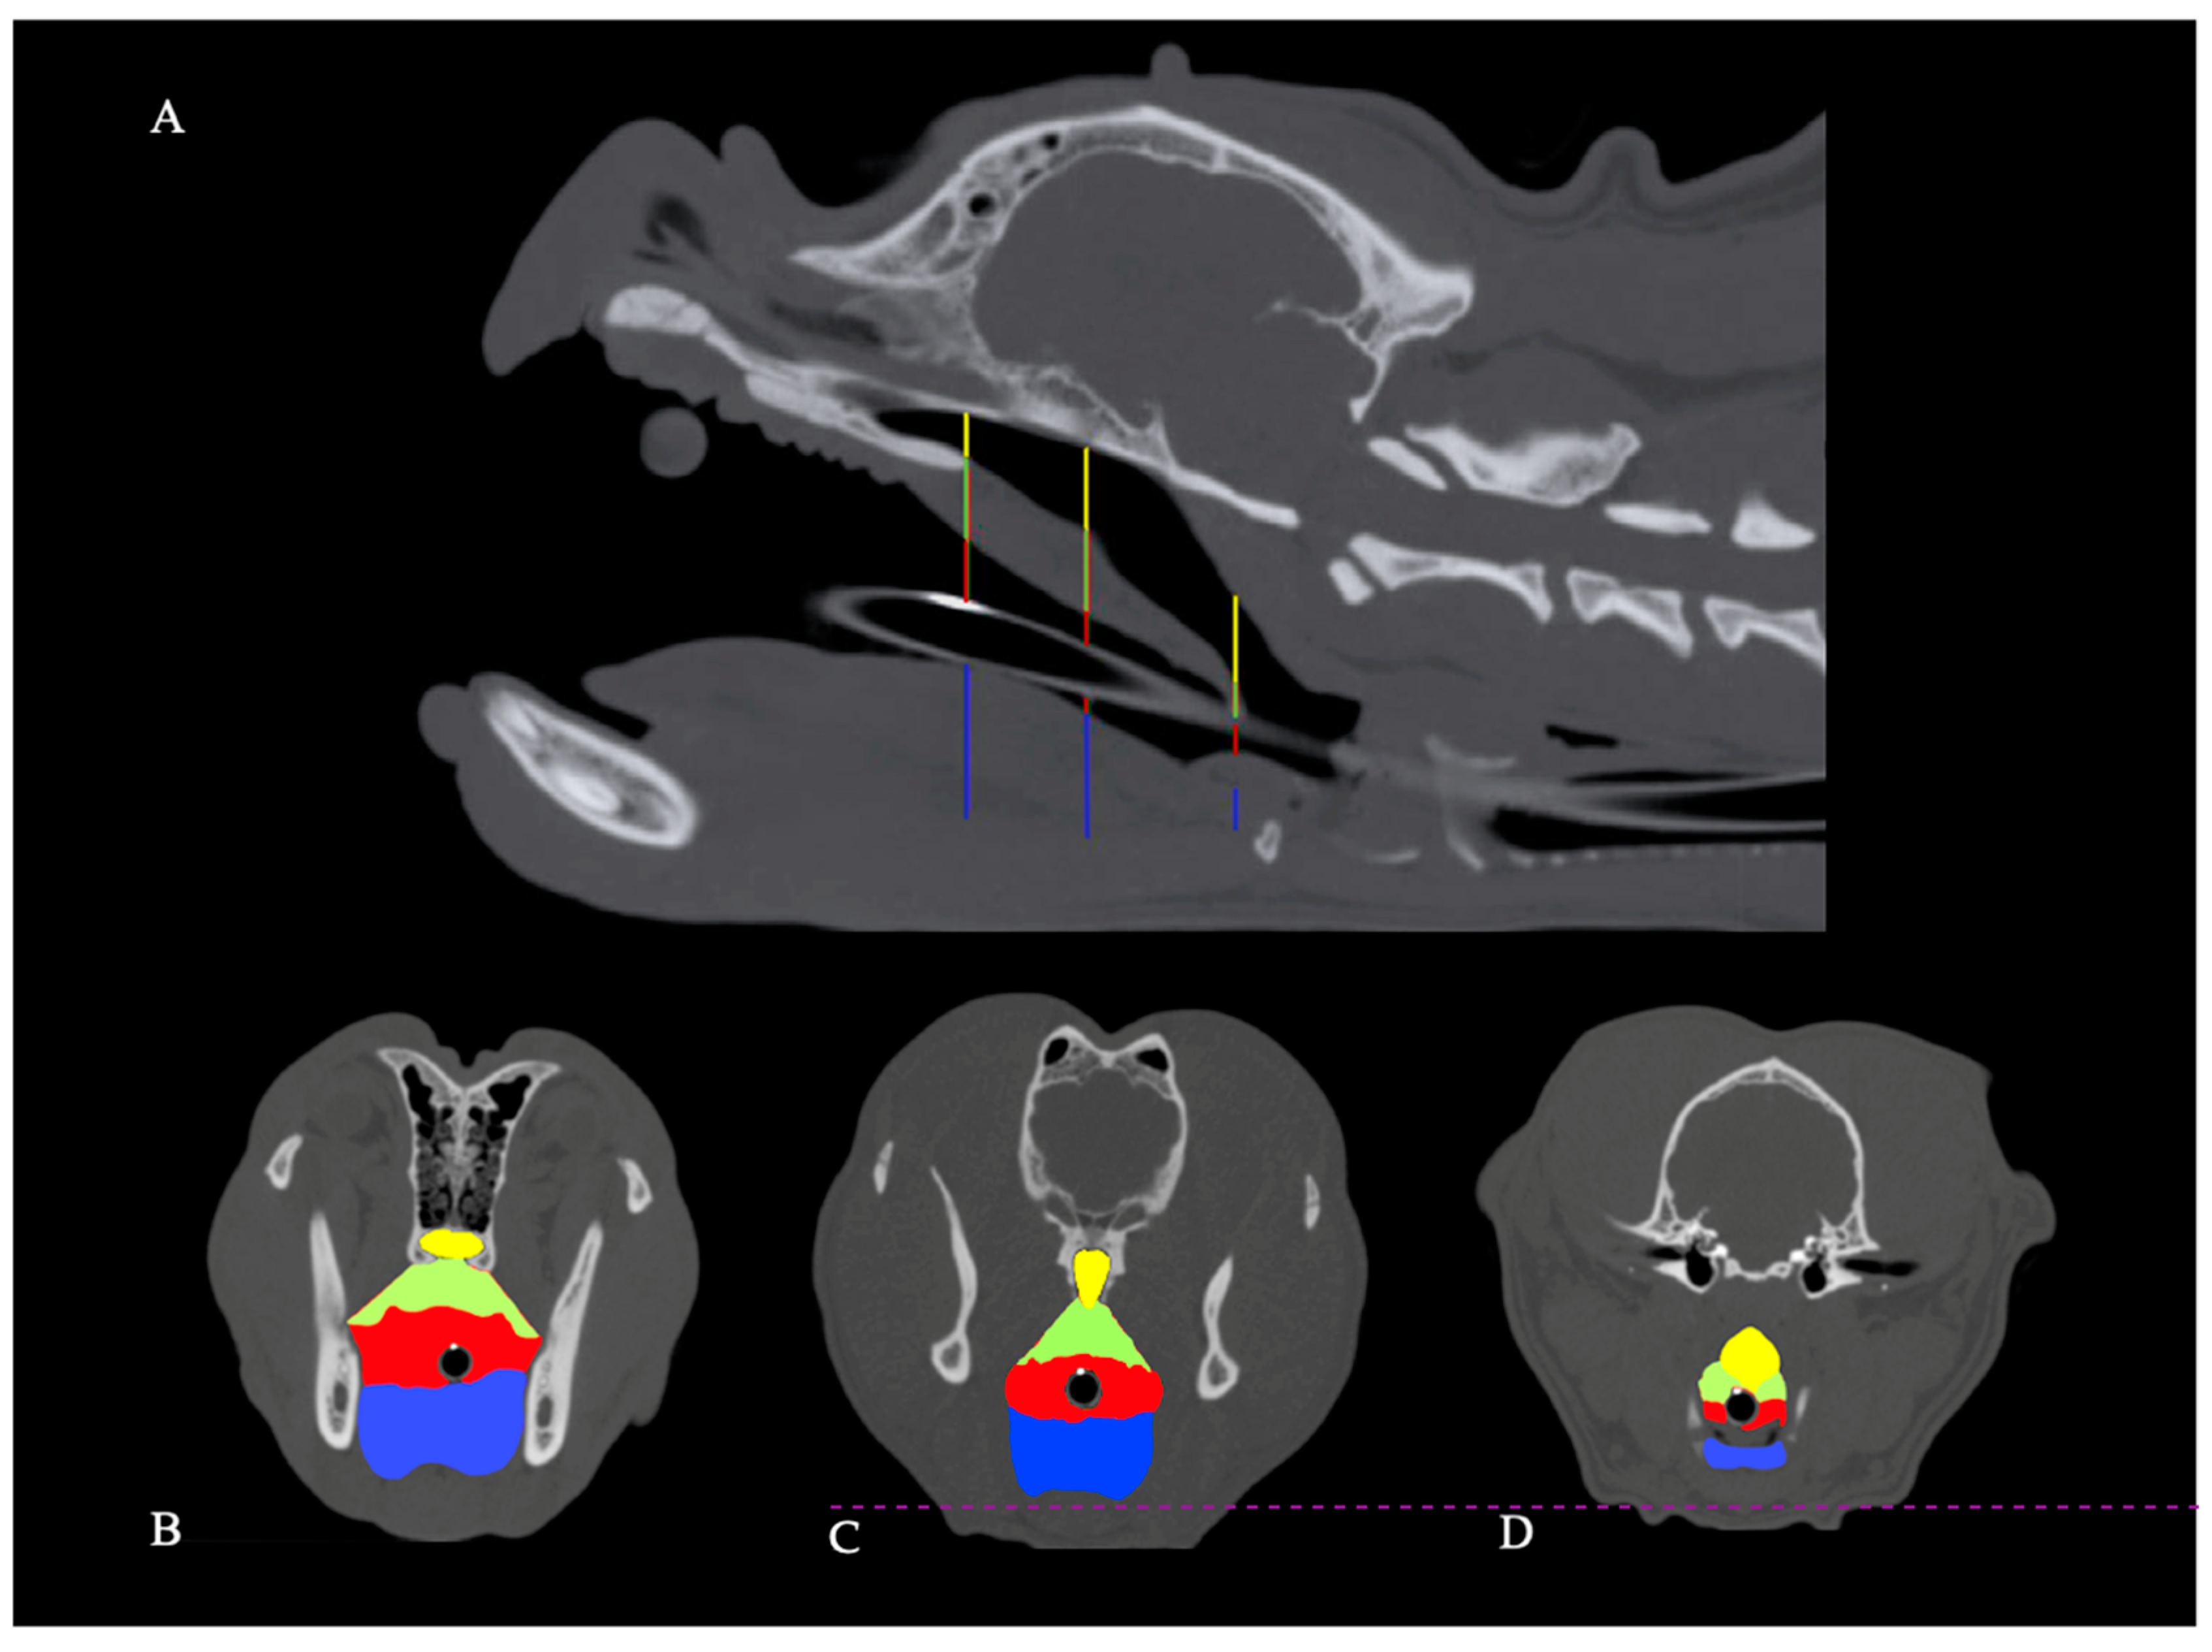

2.2. Methods

2.2.1. Computed Tomography Examination

2.2.2. Tongue Volume and Cross-Sectional Area Assessment